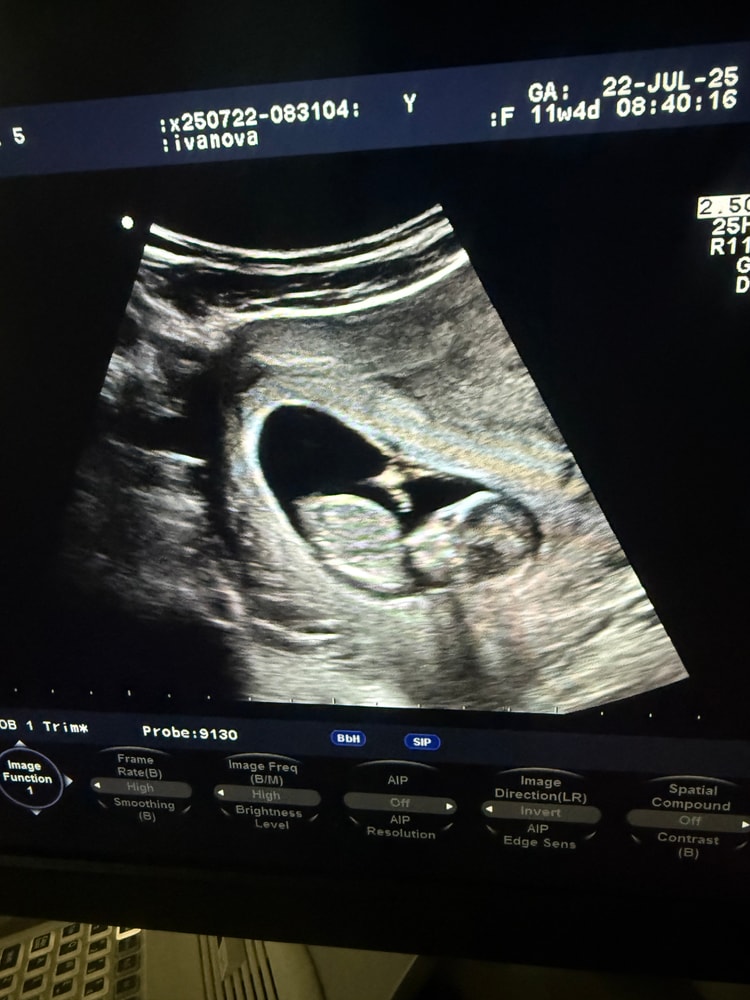

Пол на первом скрининге

Пол малышаДевочки, а всем хотя бы предположительно говорили пол на 1 скрининге ?

У меня на фото у малыша совсем не видно полового бугорка.

неужели он ещё не сформировался к 12 неделе? Или просто лежит как то другим боком и не показывает ?

но может кто-то что-то увидит на фото и может предположить пол